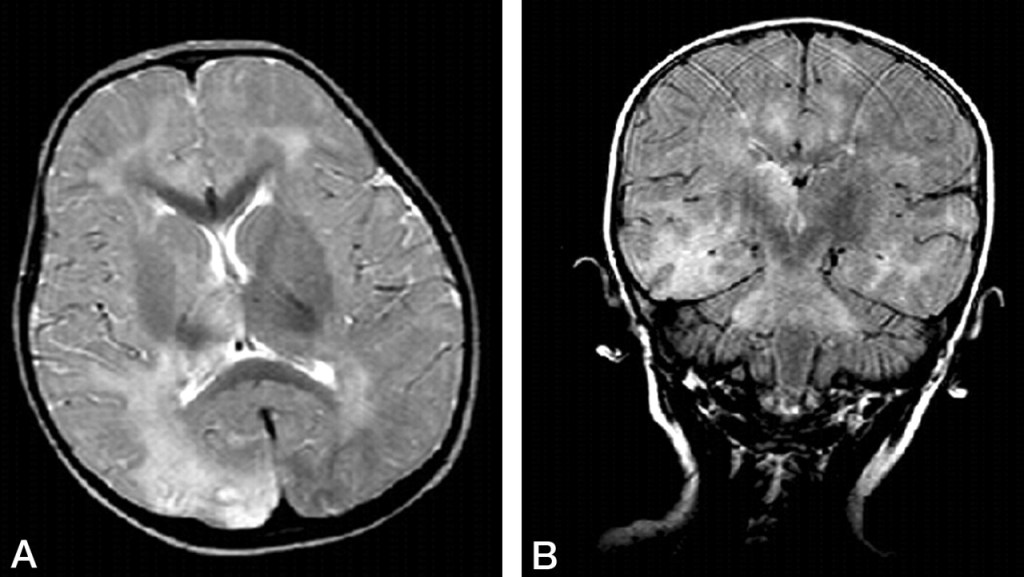

Health officials warn about subacute sclerosing panencephalitis, a rare, nearly always fatal complication that can arise years after measles. The case comes as vaccination rates dip in parts of the United States.

LA case underscores risks of SSPE, a deadly condition that can emerge years after measles as vaccination rates dip